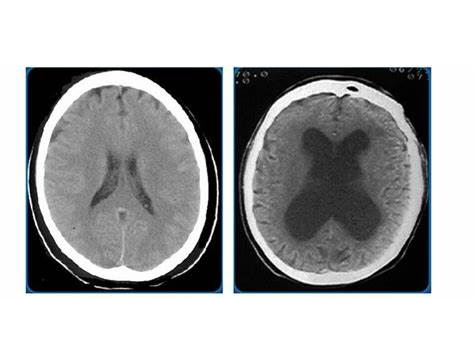

脑积水是大脑中积聚过多液体的疾病。该名称来自希腊语的组合,意为“水”和“头”。积聚的液体不是水。它是脑脊液(CSF)。它通过大脑循环,带来重要的营养,并冲走组织中的废物。通常,它被吸收到血液中。

患有脑积水时,液体的吸收速度和吸收速度之间是不平衡的。结果是它积累了。这可能导致头部增大并增加大脑周围的压力。